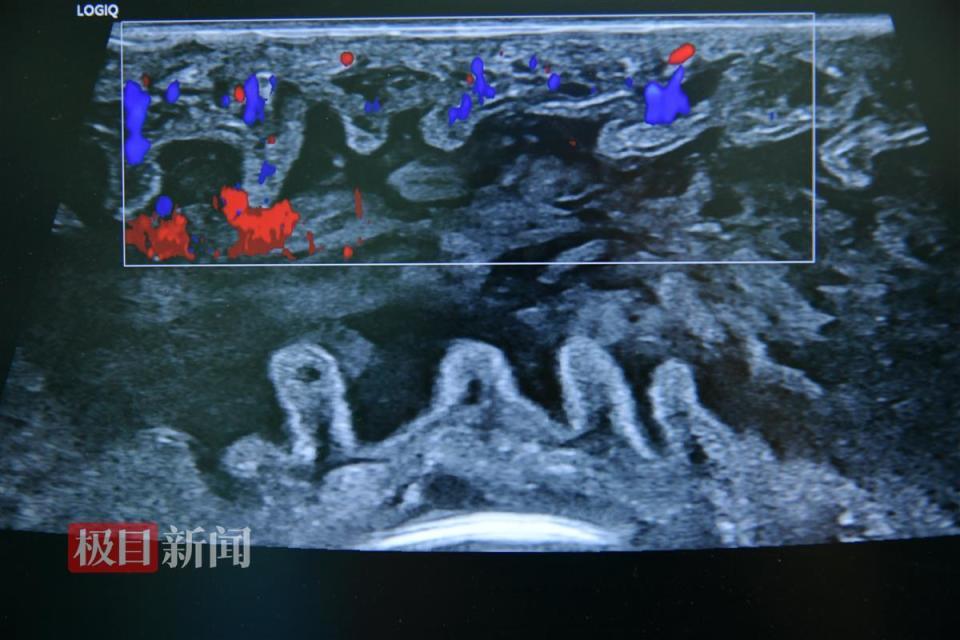

图片

移植的小肠供体恢复血流